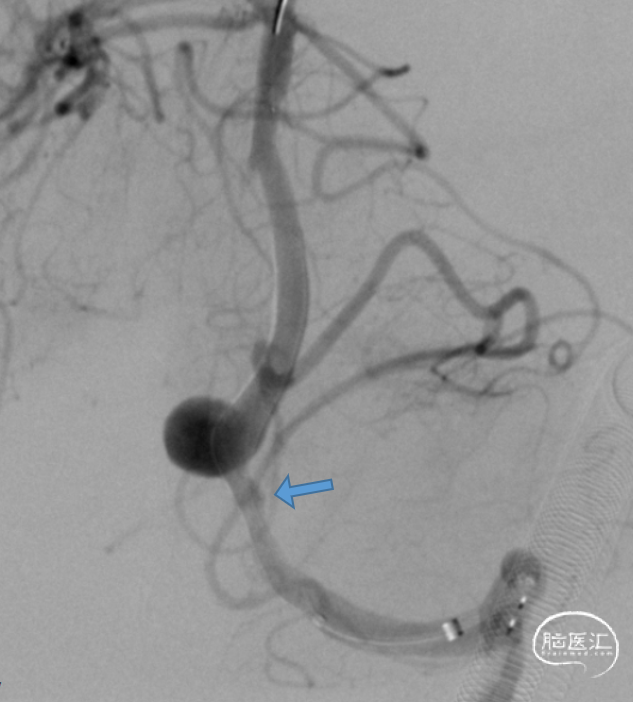

术前造影:

6F Navien到位,Phenom 27内输送J-Tube™4.25*20血流导向密网支架,顺畅到位。

头端打开良好。

J-Tube™打开过程-整体显影性能良好。J-Tube™血流导向密网支架整体释放过程,贴壁良好。

术后即刻。

术后即刻,可见动脉瘤瘤腔内血液滞留明显。

术后即刻,正侧位造影。